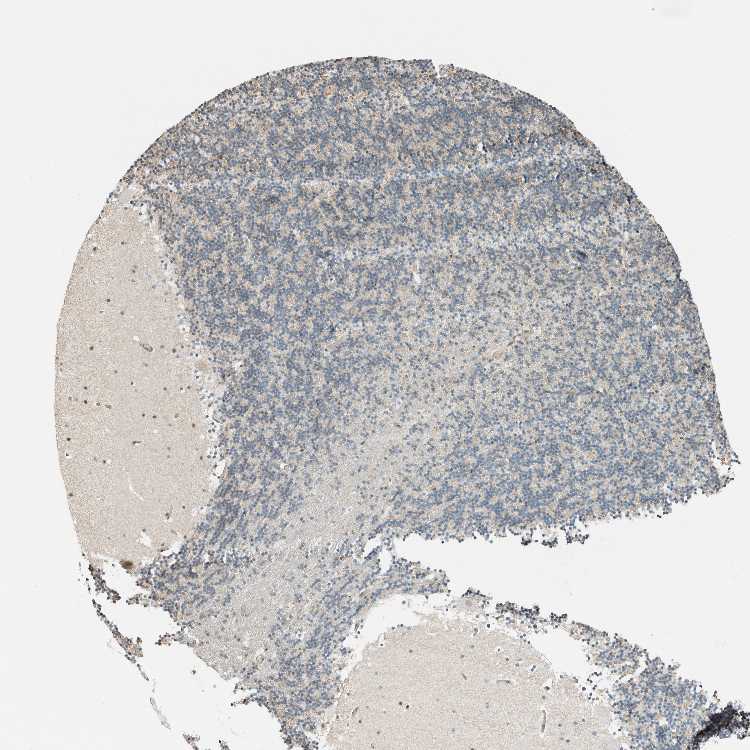

CEREBELLUM - Antibody stainingi

Antibody staining in the annotated cell types in the current human tissue is reported as not detected, low, medium, or high, based on conventional immunohistochemistry profiling in selected tissues. This score is based on the combination of the staining intensity and fraction of stained cells.

Each image is clickable and will lead to virtual microscopy that enables deeper exploration of all samples and also displays staining intensity scores, fraction scores and subcellular localization as well as patient and tissue information for each sample.

Antibody HPA021284Antibody HPA021417Antibody HPA023261Antibody HPA024312

Purkinje cells LowNot detectedLowNot detected

Cells in granular layer Not detectedNot detectedNot detectedNot detected

Cells in molecular layer Not detectedNot detectedLowNot detected